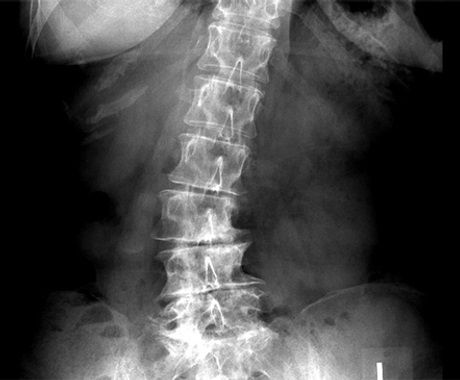

ΣΚΟΛΙΩΣΗ ΚΑΙ ΚΡΑΝΙΟΪΕΡΗ ΘΕΡΑΠΕΙΑ

Η Ιδιοπαθής σκολίωση θεωρείτε αγνώστου αιτιολογίας. Η Κρανιοϊερή Θεραπεία (Upledger) επιχειρεί να διαλευκαίνει το μυστήριο αποδίδοντας την αιτία μέσα στο Κρανιοϊερό και Περιτονιακό σύστημα του σώματος. Η προσαρμογή αυτών των συστημάτων σε πρότυπα τάσης, μπορεί να αποτελεί βασικό παράγοντα στη δημιουργία και την διατήρηση της σκολίωσης.